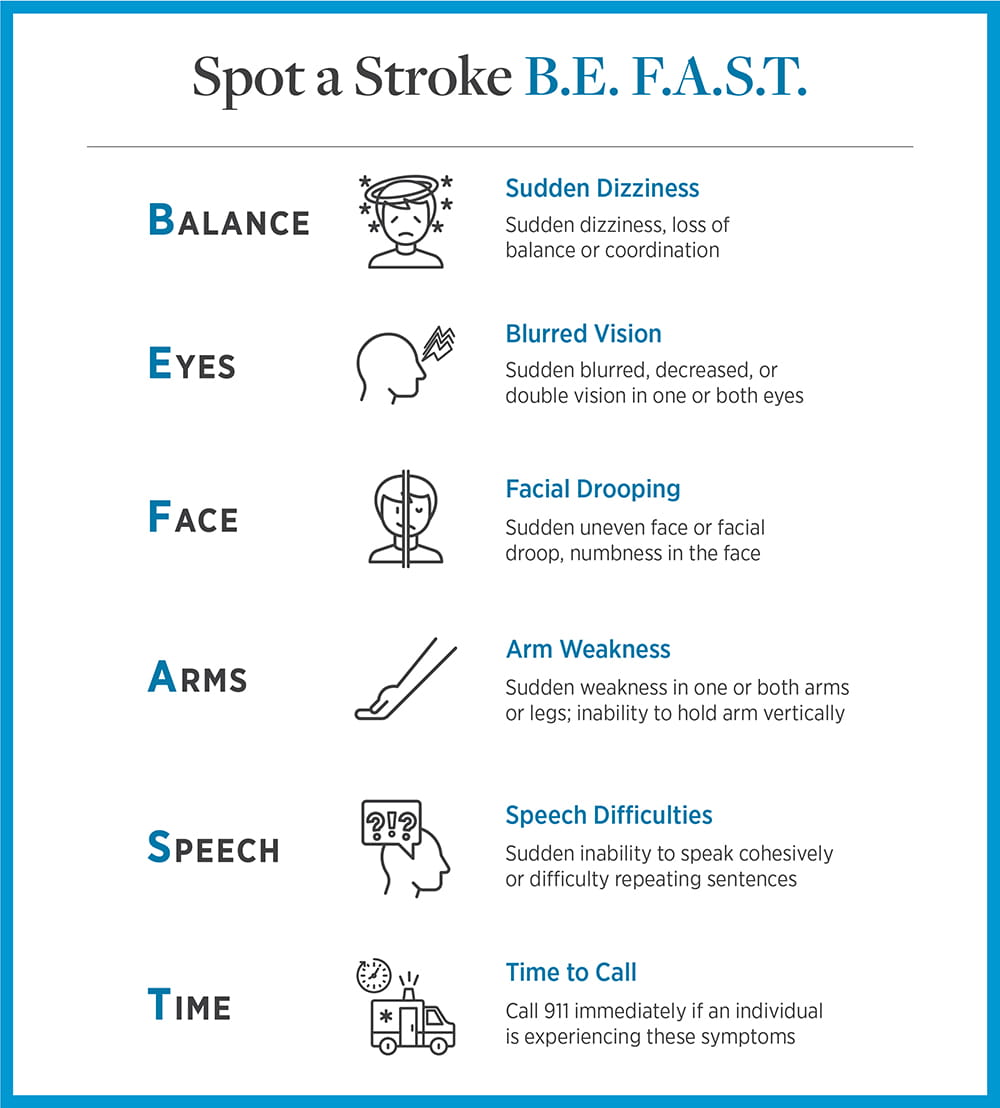

The signs and symptoms of a stroke include:

- Sudden dizziness

- Blurred vision

- Facial drooping

- Weakness on one side of the body

- Speech difficulties

If someone is having a stroke, you should B.E. F.A.S.T.

Millions of brain cells are lost every minute during a stroke. It is critical to get advanced medical care as quickly as possible. Call 911 immediately.